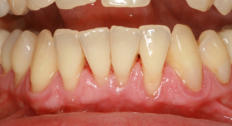

Bei der Parodontitis (Entzündung des Zahnbettes oder des Zahnhalteapparates) handelt es sich um eine chronische Erkrankung, die zum Abbau der zahntragenden Gewebe führt und mit Zahnfleischtaschen, erhöhter Lockerung des Zahnes, evtl. Schmerzen, bis zum Zahnausfall einhergeht. Parodontitis kann einzelne oder alle Zähne befallen und in seltenen Fällen schon bei Kindern und Jugendlichen auftreten. Sie verläuft lange still und unbemerkt und wirkt sich auch schädigend auf das Herz-Kreislaufsystem, Körperfunktionen und Organe aus.